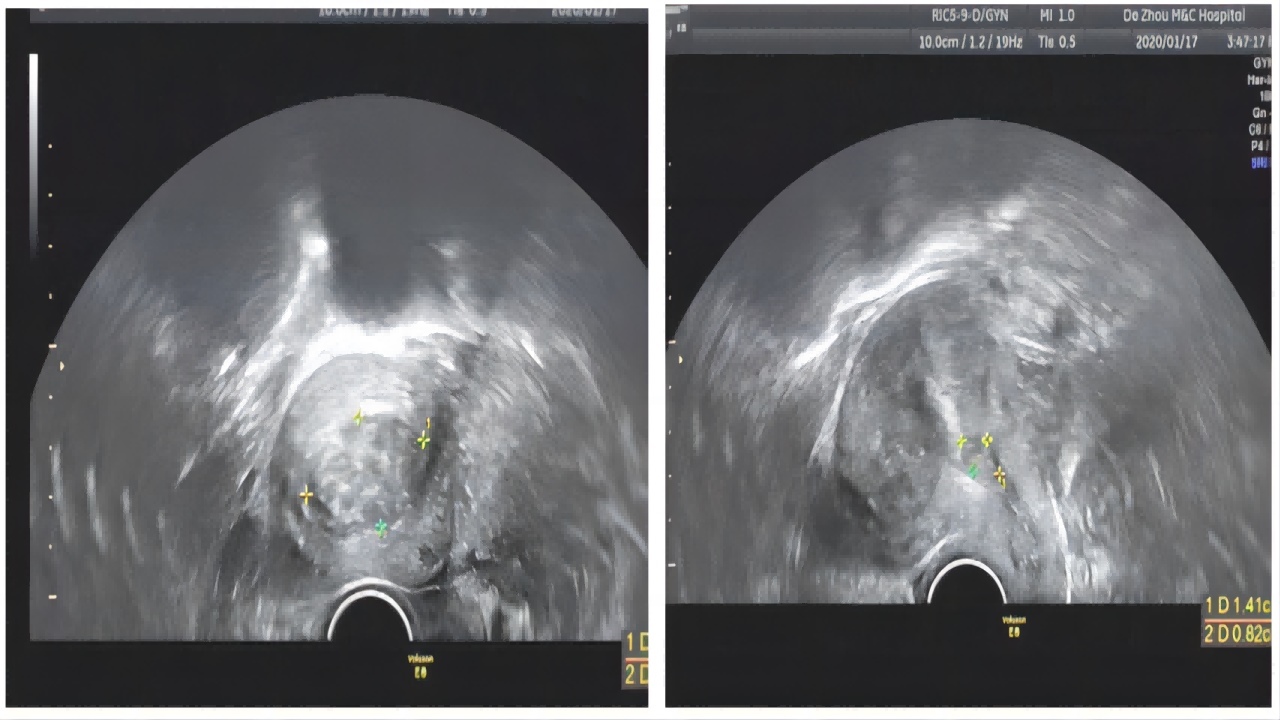

辅助检查:2020-01-17B超:子宫后位,宫颈长约32mm,宫体大小约60×54×56mm,外形规则,肌层回声不均质。子宫后壁肌壁间见36×23mm的低回声,距离浆膜面5mm,CDFI:周边见点片状血流信号。内膜厚度7mm,清晰居中;宫腔内未见节育器回声。宫腔下段见14×8mm的低回声,边界清,压迫内膜,CDFI:周边见星点状血流信号。右卵巢大小:25×15mm,左卵巢大小:27×17mm,双侧附件区未见明显异常回声及异常血流信号。检查提示:子宫肌瘤宫腔下段低回声(不排除黏膜下肌瘤可能)。

2020-01-17门诊宫腔镜检查:宫颈管见多发舌状小息肉,宫腔形态失常,左侧壁下段见一肌瘤样占位,大小约1.5×0.9cm,超声监测可见子宫后壁偏左侧肌壁间肌瘤,大小约4×3cm,基底层距子宫浆膜层约0.5cm,距离内膜面2mm,降压后未见明显内突,双侧输卵管开口可见。内膜:厚,出血:点。术中诊断:子宫肌瘤I型、III型、宫颈息肉。